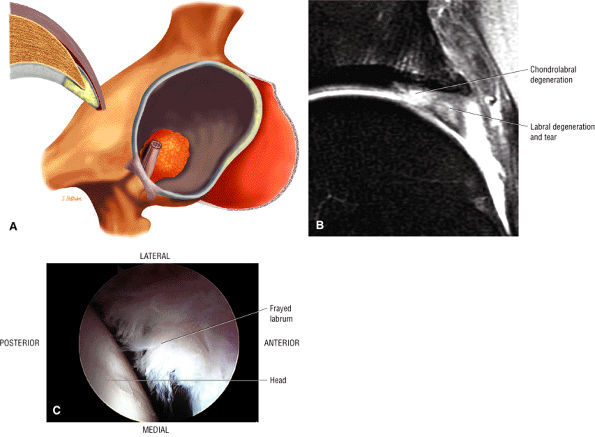

FIGURE 3.148 ● Coronal (A) and axial (B) T1-weighted images depicting the gluteus medius attachment to the superoposterior facet on posterior coronal and axial images. The medius and minimus attachments are shown on the axial image (B).

|

from the lower back. In both cases, it is important to differentiate between bursitis and lumbar disease. Rheumatoid arthritis is also associated with trochanteric bursitis. Treatment consists of activity modification, physical therapy, and nonsteroidal anti-inflammatory drugs. Occasionally, local steroid injection and, less commonly, surgical intervention play a role.

![]() |

FIGURE 3.149 ● Location of the three greater trochanter bursae (the trochanteric or subgluteus maximus bursa, the subgluteus medius bursa, and the subgluteus minimus bursa). (A) 3D color illustration. (B) Coronal color section.

FIGURE 3.150 ● (A) Arthroscopic view of the trochanteric or subgluteus bursa. The trochanteric bursa has a contour parallel to the posterior facet. (B) Coronal FS PD FSE image showing the linear contour of greater trochanteric bursa in a patient with associated tendinosis of the gluteus minimus tendon.

FIGURE 3.151 ● Subgluteus medius bursa involvement in a patient with avulsion of the minimus and partial tear of the medius tendons. (A) Sagittal FS PD FSE image. (B) Coronal FS PD FSE image.

FIGURE 3.152 ● Subgluteus minimus bursal inflammation associated with tendinosis and partial tear of the gluteus minimus tendon. (A) Coronal FS PD FSE image. (B) Sagittal FS PD FSE image.